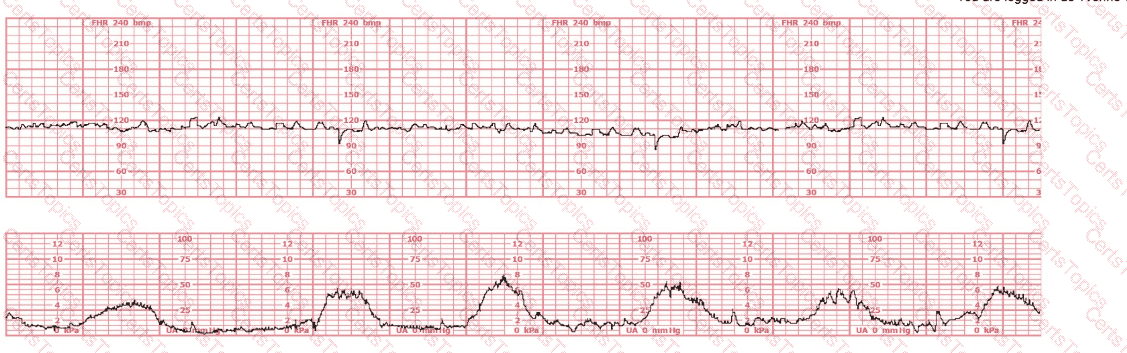

This fetal heart rate tracing is of a woman in labor with dichorionic-diamniotic twins at 36-weeks gestation, 4 cm dilated. She is on oxygen via face mask. Based on the fetal heart rate tracing, what is the most appropriate action?

(Tracing A = black; Tracing B = blue)

The black pattern represents the heart rate pattern for Baby A. The blue pattern represents the heart rate pattern for Baby B. A possible etiology of the baseline fetal heart rate of Baby A is: